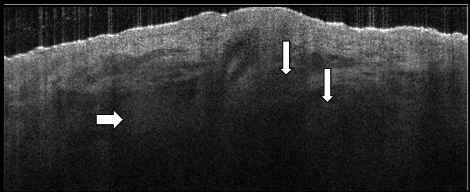

• Hyporeflective ovoid structures associated with the hair matrix

• Possess a “hazy” granular texture due to cell aggregations and secretary lumen spaces within the gland tissue

• Located within the reticular dermis, full gland not usually seen